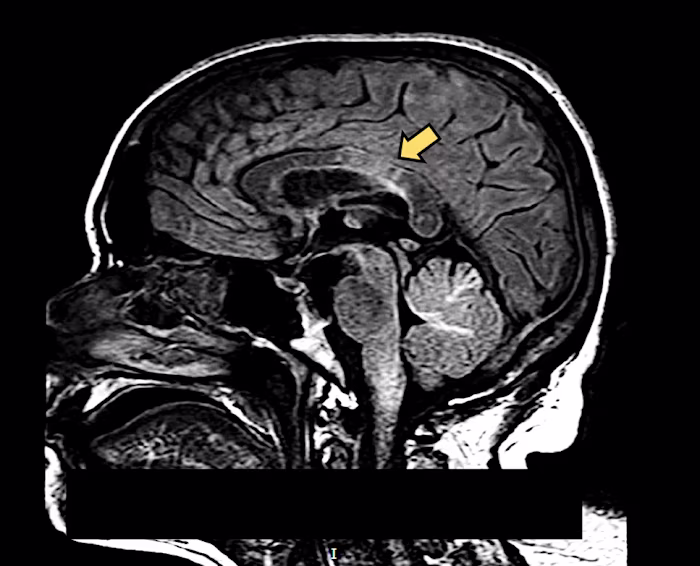

However, VA is not without its pitfalls in the investigation of natural deaths. Differences in the organ-specific sensitivity of VA are observed. Due to the inability to differentiate AM injury from PM changes, the diagnosis of ischaemic brain injury and myocarditis is proven to be problematic.20,30 Furthermore, PM-MRI alone has not proven to be adequate to opine whether the hypoxic–ischemic changes are an agonal manifestation or PM change/artefact.

Since the 1300s autopsies, also known as necropsies, have been carried out as part of death investigations for both academic and medico-legal purposes. 1 In the last three decades, the development of technology has made a significant impact on the evolution of autopsy techniques. Richard Dirnhofer first introduced the concept of ‘virtual autopsy (VA)’ or ‘virtopsy’ by combining innovative technology with conventional autopsy (CA). The result is a non-invasive method of conducting autopsies employing imaging modalities such as X-ray, computed tomography, magnetic resonance imaging and so on. 1